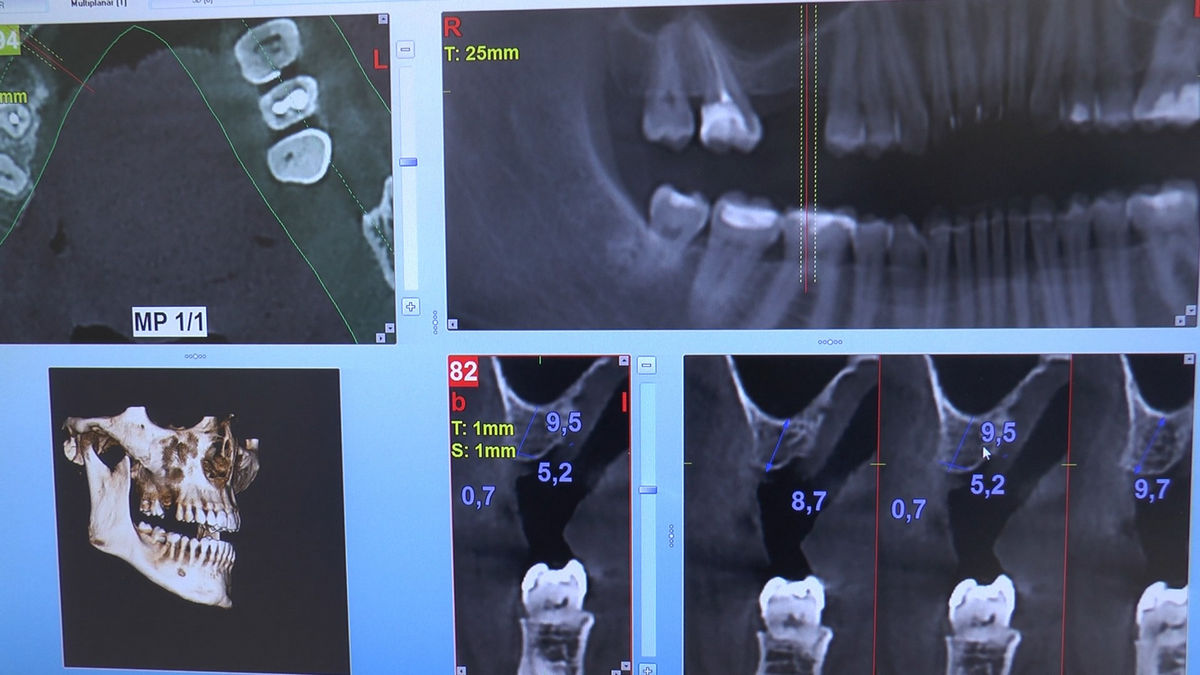

Practiculum Implantologii – Sezon V/B, sesja 8, część 4